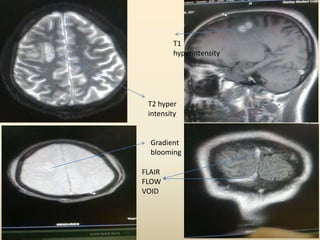

 MRI brain shows T1 hyperintense / non

suppressible T2 hyperintensity in the right

high parietal lobe. The lesion shows

peripheral blooming in T2 gradient sequence

suggestive of hemorrhage.

 Absence of flow voids in mid sagittal and

transverse sinus in FLAIR images suggestive

of sinus thrombosis

 T1 hyperintensity noted in superior sagittal

sinus and right transverse sinus suggestive of

thrombosis.

 MR venography confirms the evidence of

thrombosis in superior sagittal sinus and right

transverse sinus.

T2 hyper

intensity

Gradient

blooming

T1

hyperintensity

FLAIR

FLOW

VOID